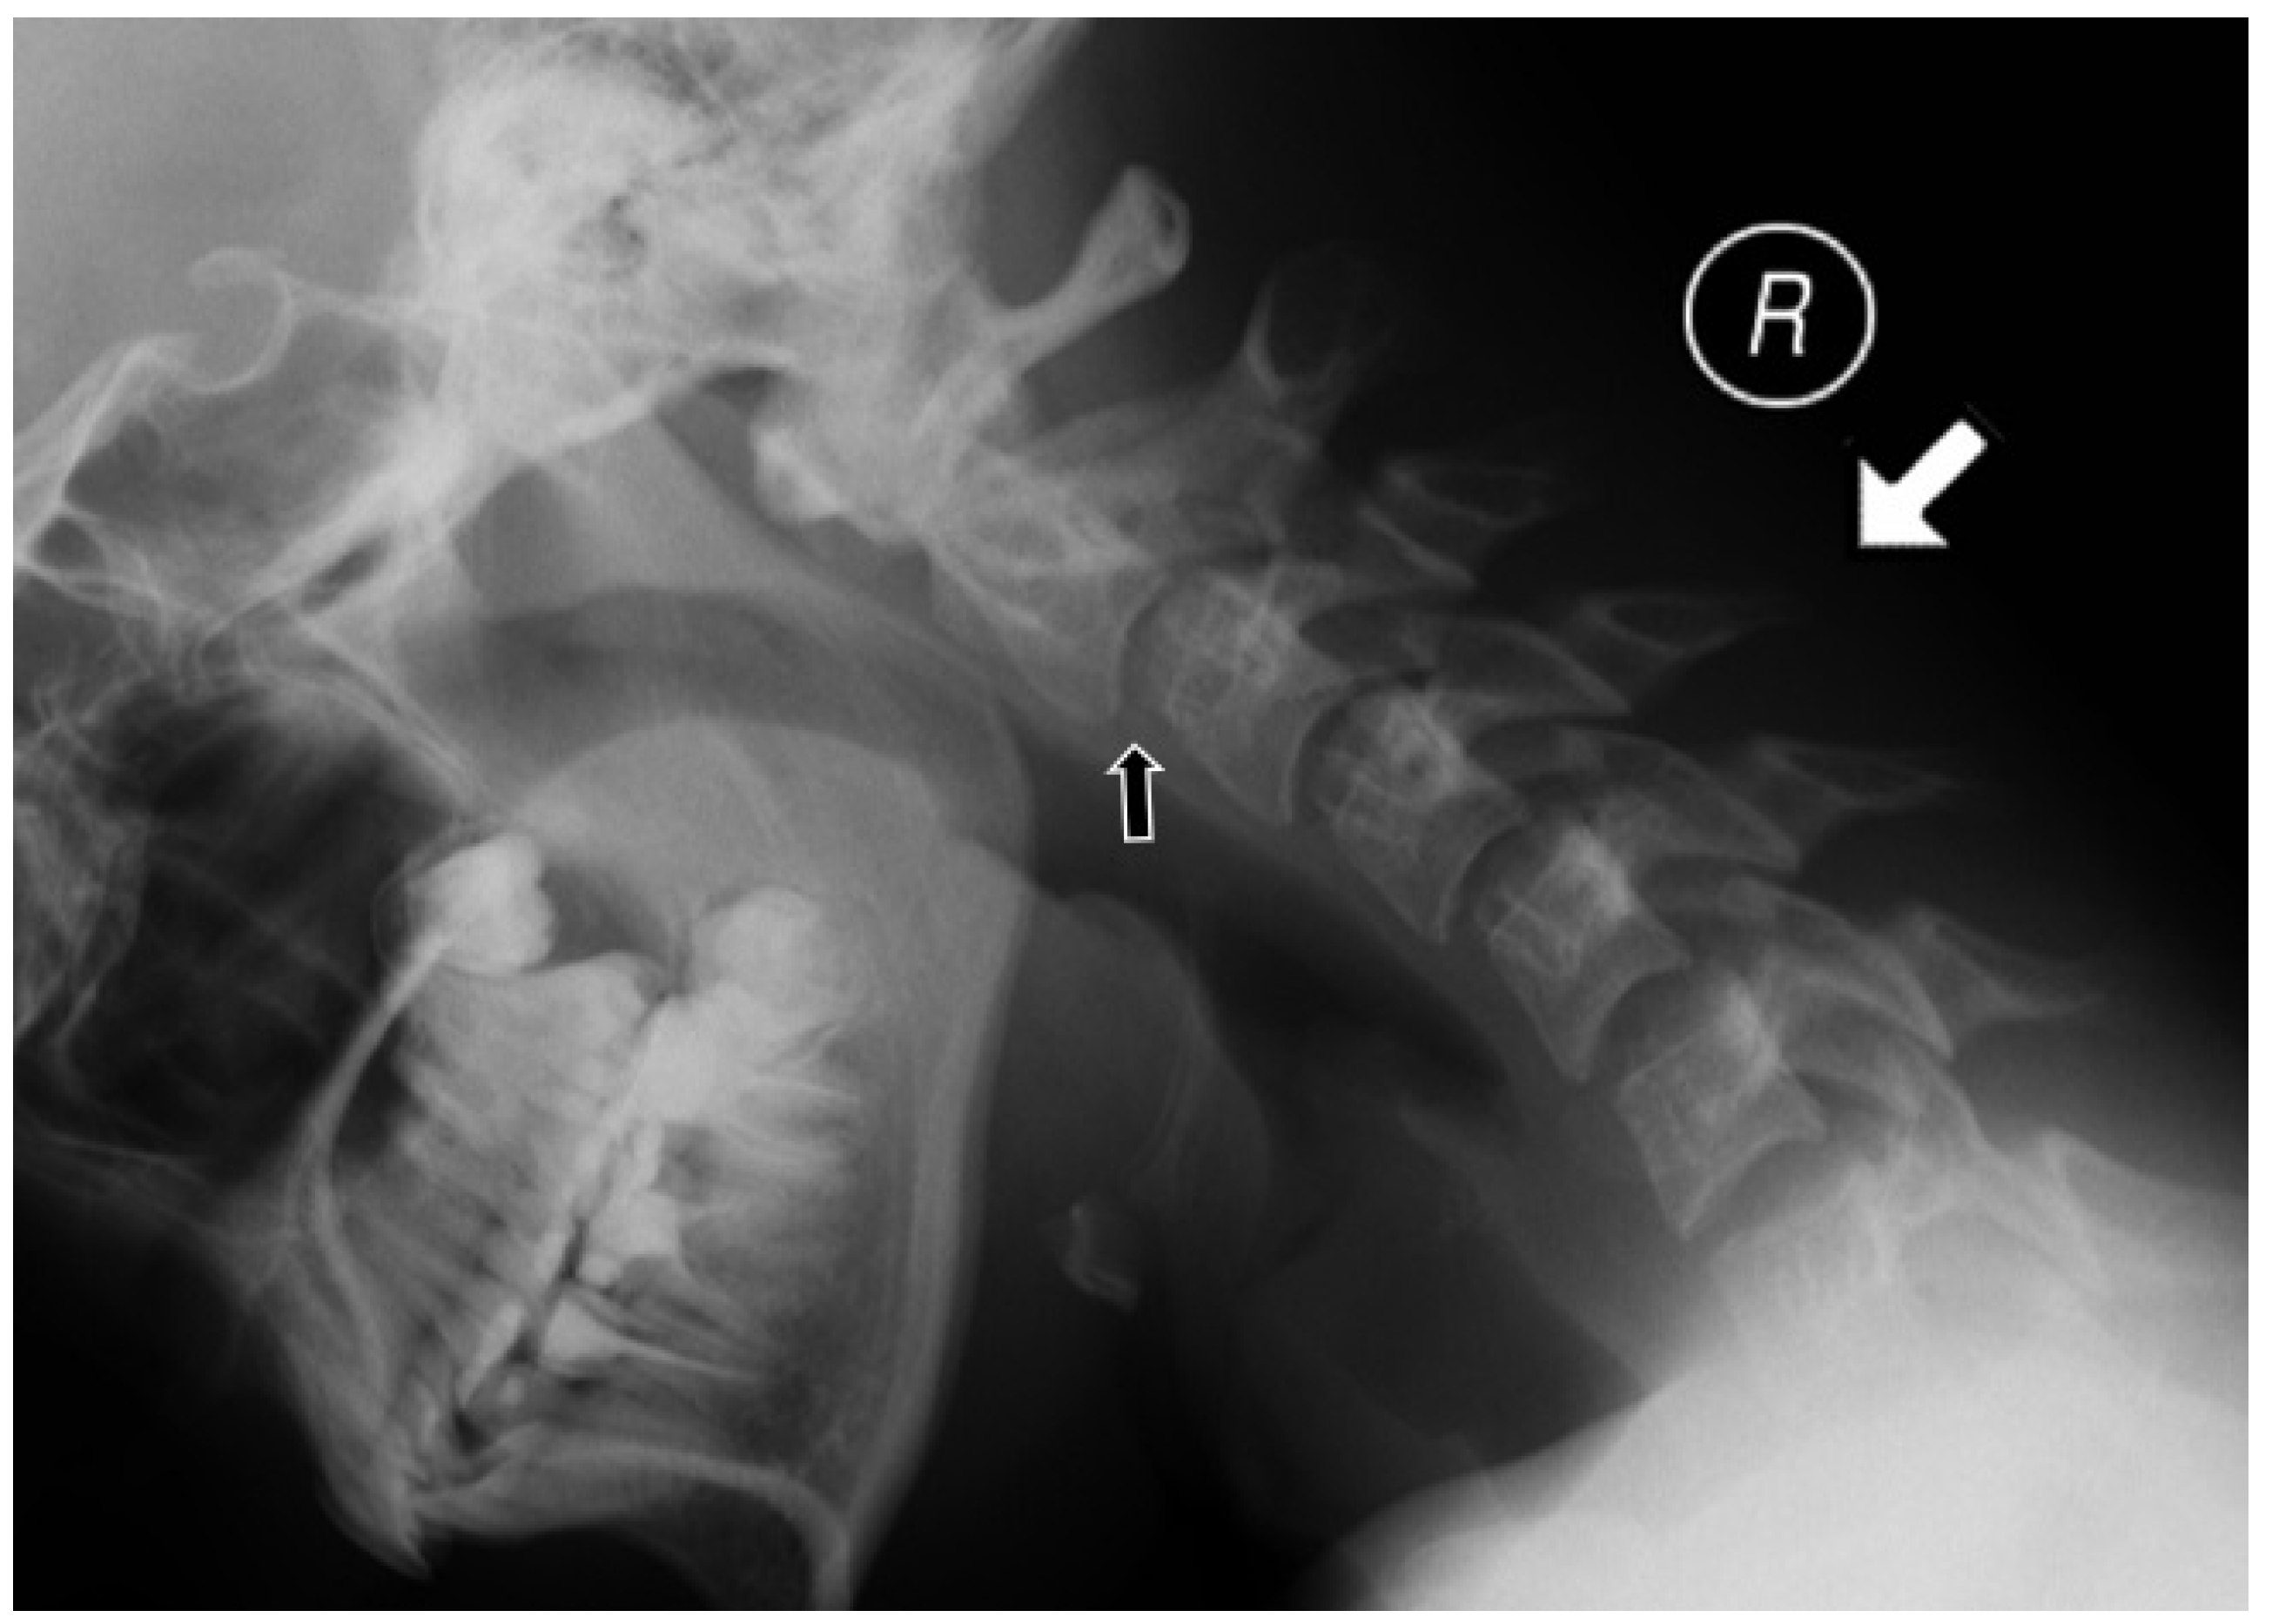

For the MRI examinations, a 1.5 T MRI scanner (Siemens Avanto) and the head/neck 8-channel coil were used. The protocol included coronal T2-weighted (w), axial T2w, sagittal T1w, T2w, T2w TIRM (turbo inversion recovery magnitude) sequences, and postcontrast T1w with fat saturation. Only one patient received intravenous contrast. At the atlanto-axial level, bone marrow oedema (BME), effusion, pannus, subluxations, cysts and erosions were looked for (Figure 2). At the subaxial level, BME, apophyseal joint ankylosis, SAS, and vertebral or disc hypoplasia were searched for [10,11]. Anterior AAS was diagnosed when a distance between the posterior aspect of the anterior arch of the atlas and the anterior aspect of the dens exceeded 5 mm [12] (Figure 3).

Anterior AAS was diagnosed in dynamic radiography (2 cases) but was not confirmed in MRI. Regarding abnormalities that are diagnosed by means of radiography and MRI (Table 3), SAS was seen more commonly on radiographs than MRI.

Figure 3. Lateral radiograph in neutral position in a 12-year-old boy (the same patient as in Figure 2) showing anterior atlantoaxial subluxation 6 mm (white line).